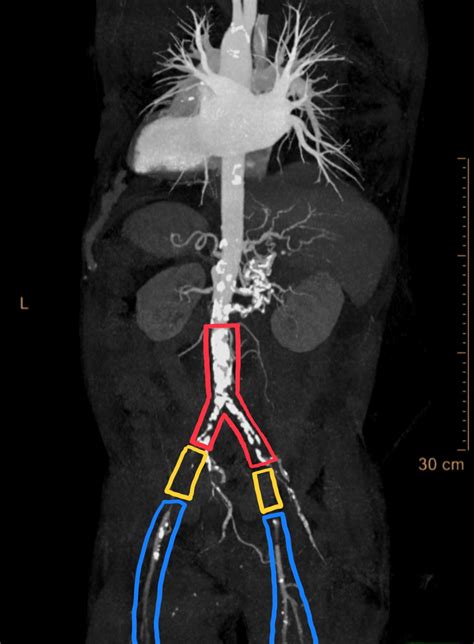

Aortoiliac Occlusive Disease (AIOD), often referred to as Leriche syndrome when it involves the complete occlusion of the distal abdominal aorta, represents a severe form of peripheral artery disease (PAD). This condition occurs when the iliac arteries—the major vessels that branch off the abdominal aorta to supply blood to the lower extremities—become narrowed or blocked due to the accumulation of plaque. Because these vessels serve as the primary "highway" for oxygen-rich blood traveling to the legs, any obstruction can lead to debilitating symptoms, ranging from intermittent claudication to critical limb ischemia. Understanding the nuances of this condition, from early warning signs to modern intervention strategies, is vital for maintaining cardiovascular health and mobility.

CTA / MRA Anatomic mapping Provides detailed 3D images of the aorta and iliac bifurcations.

Catheter Angiography Invasive gold standard Used primarily during intervention to visualize flow while treating the blockage.